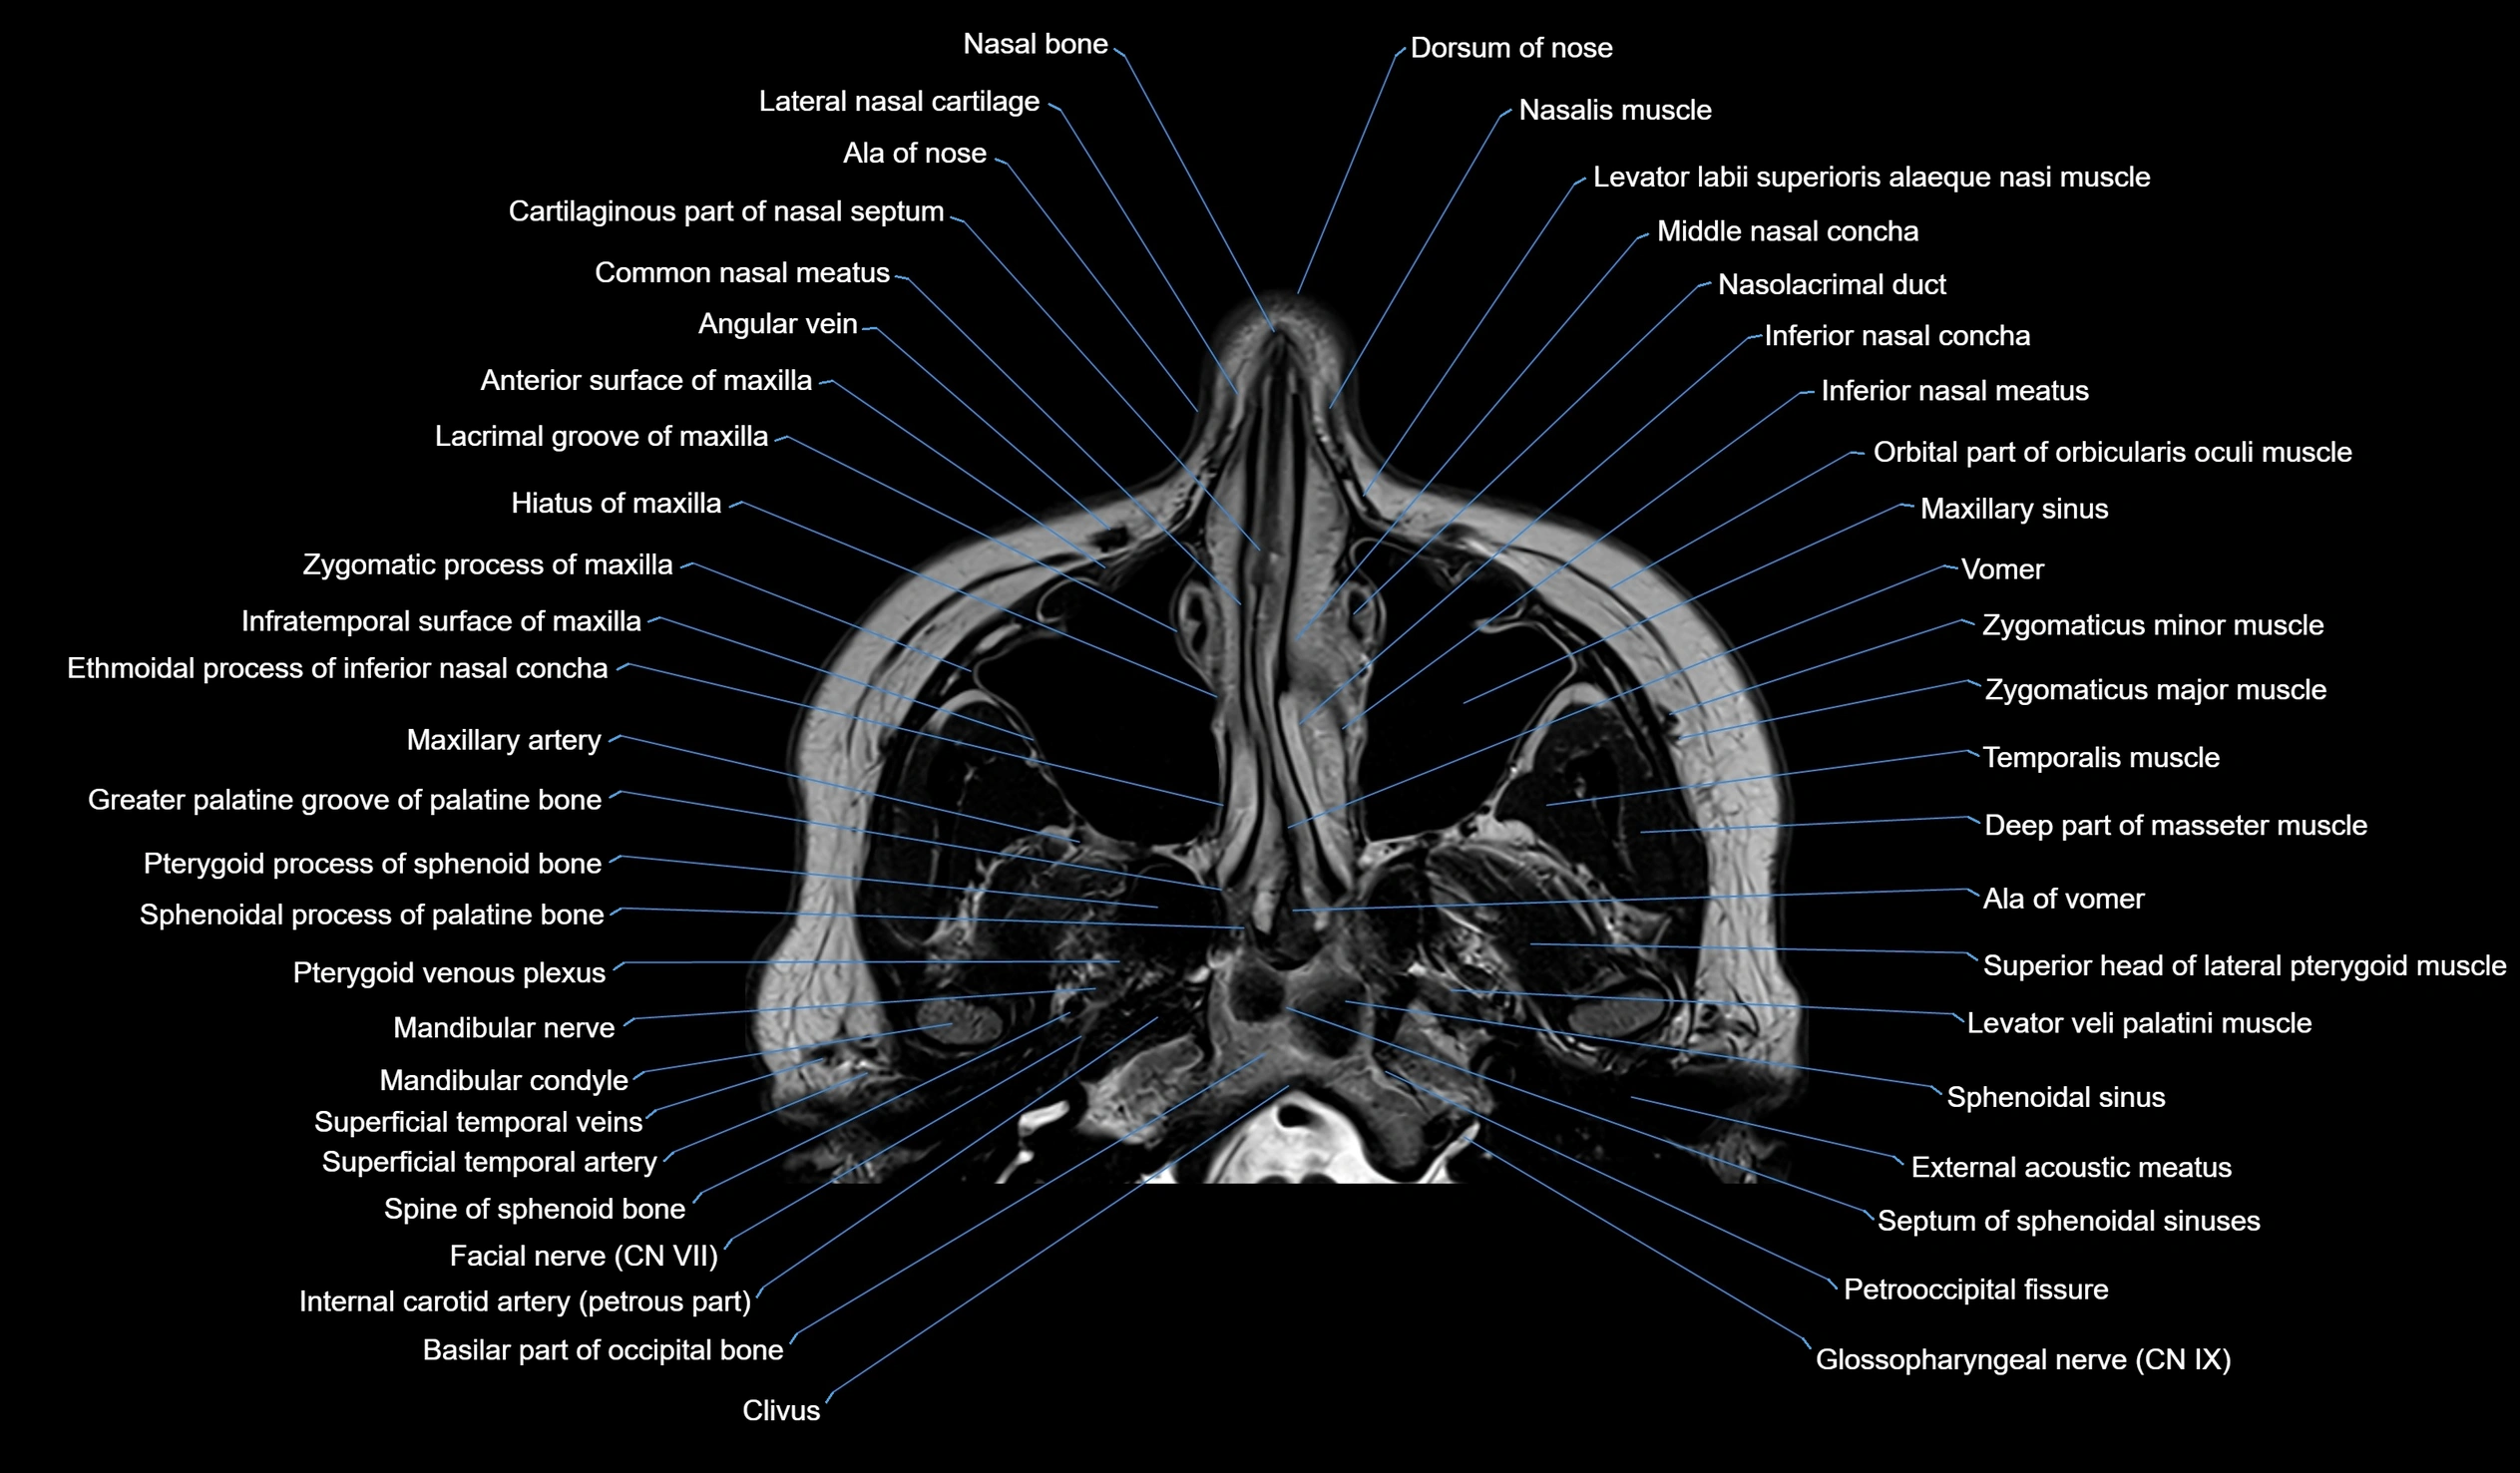

MRI images